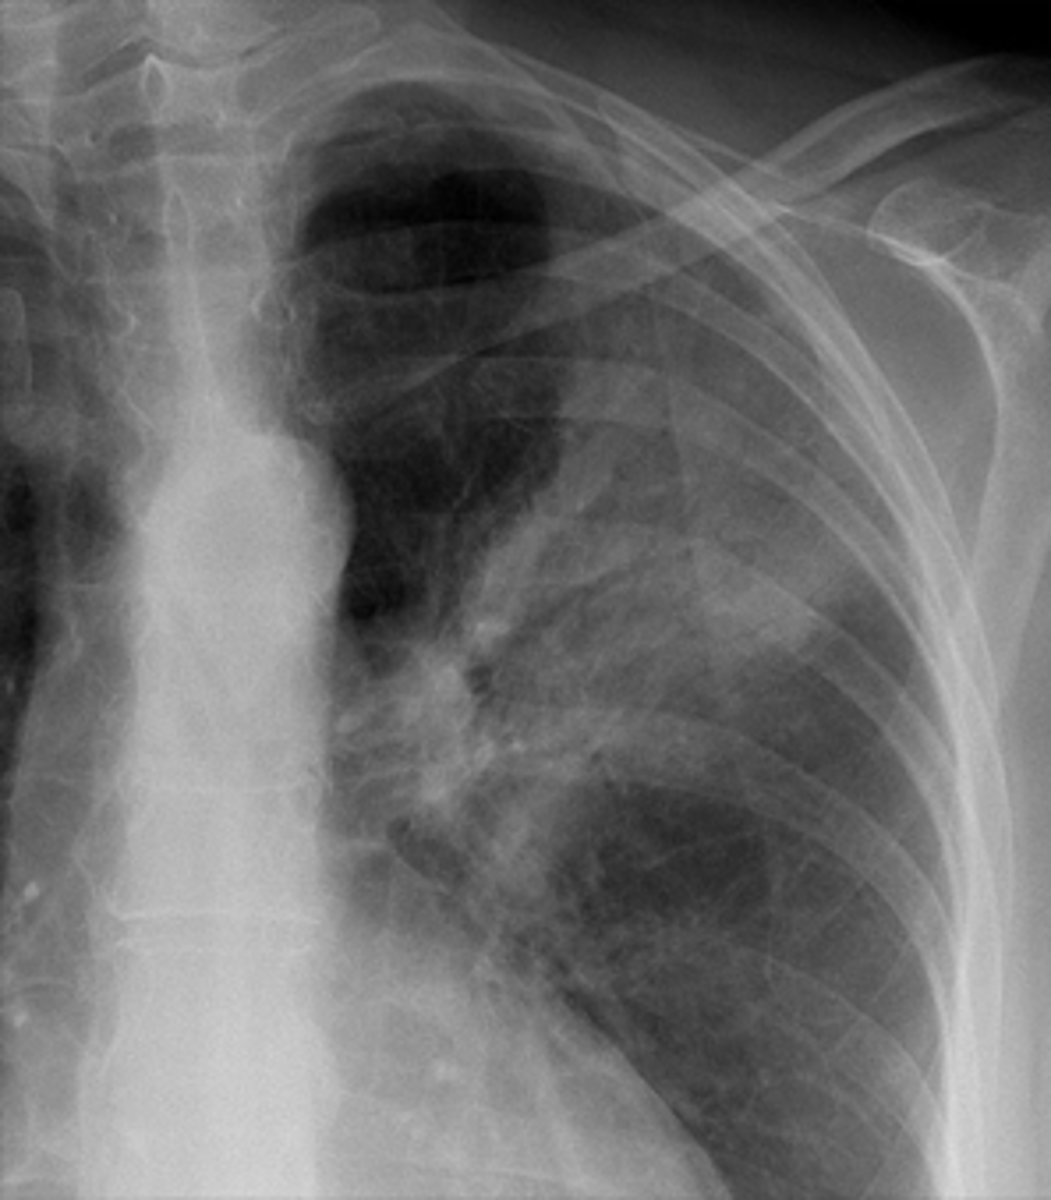

Pancoast tumor